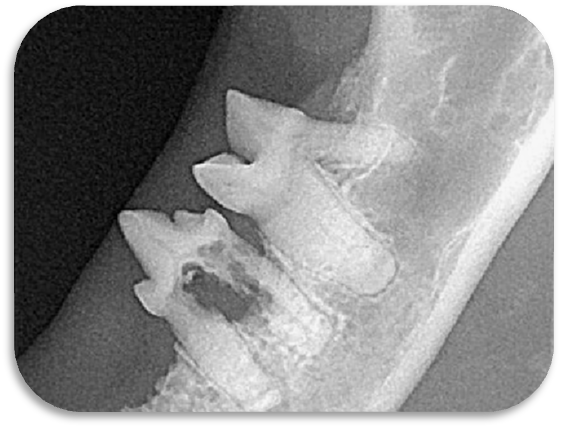

▲院内新进牙科DR设备之一

▲部分牙科DR效果展示图(可左右滑动)

什么是DR?

DR检查是影像科常用的一种检查方法,它又称为数字化X射线摄影系统,相对于传统的拍片子检查,它的辐射量更小,检查的时间更短,片子的质量也更高